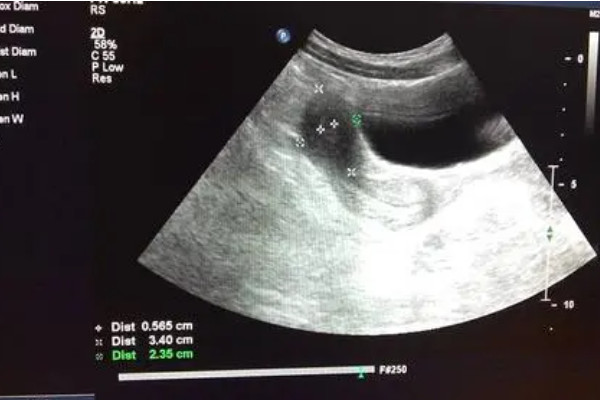

經常在圈子裡看到姐妹們在諮詢腹腔鏡的問題,當時看得我覺得這個手術是個很恐怖的事情,但當我親身去體驗了這個手術後其實覺得也沒有什麼,那麼今天就以自身的經歷分享一下這個好像很“可怕”的手術。瞭解敵人,才能戰勝敵人。希望姐妹們都能順順利利擁有自己的小孩。免受各種手術的苦。腹腔鏡知識早知道因為正常備孕一年不懷,查了各種基礎檢查沒問題。醫院B超監測排卵幾個週期後還是無果。這個時候,醫生就提出做宮腹腔鏡手術,...